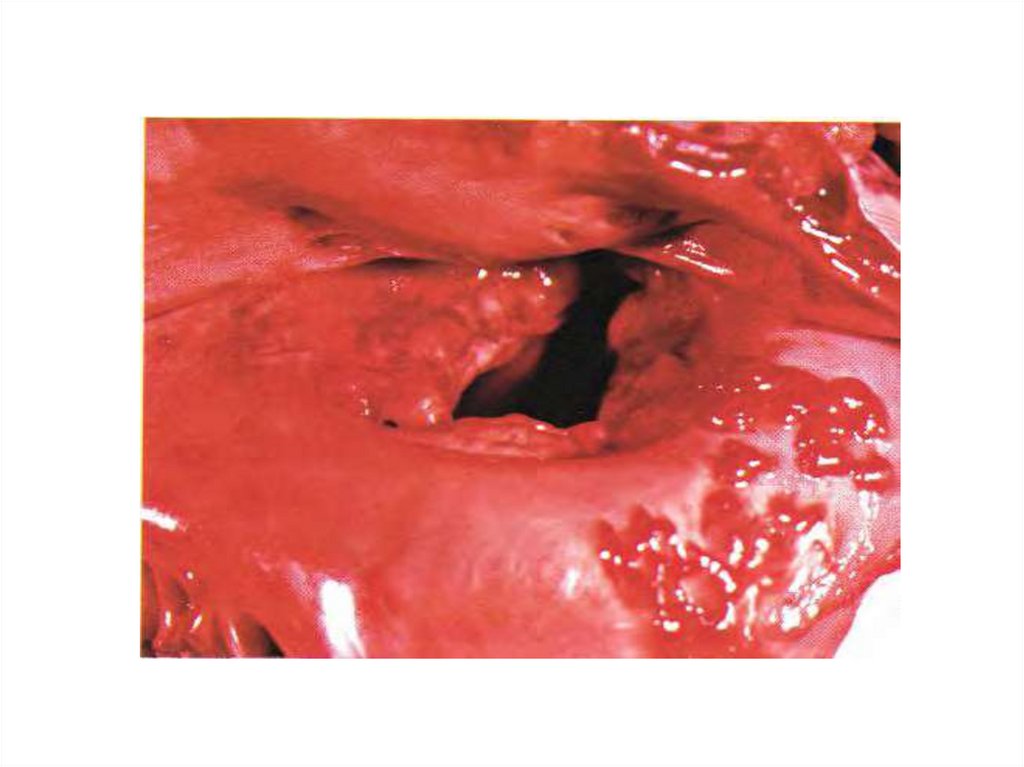

30. Образование фиброзного кольца